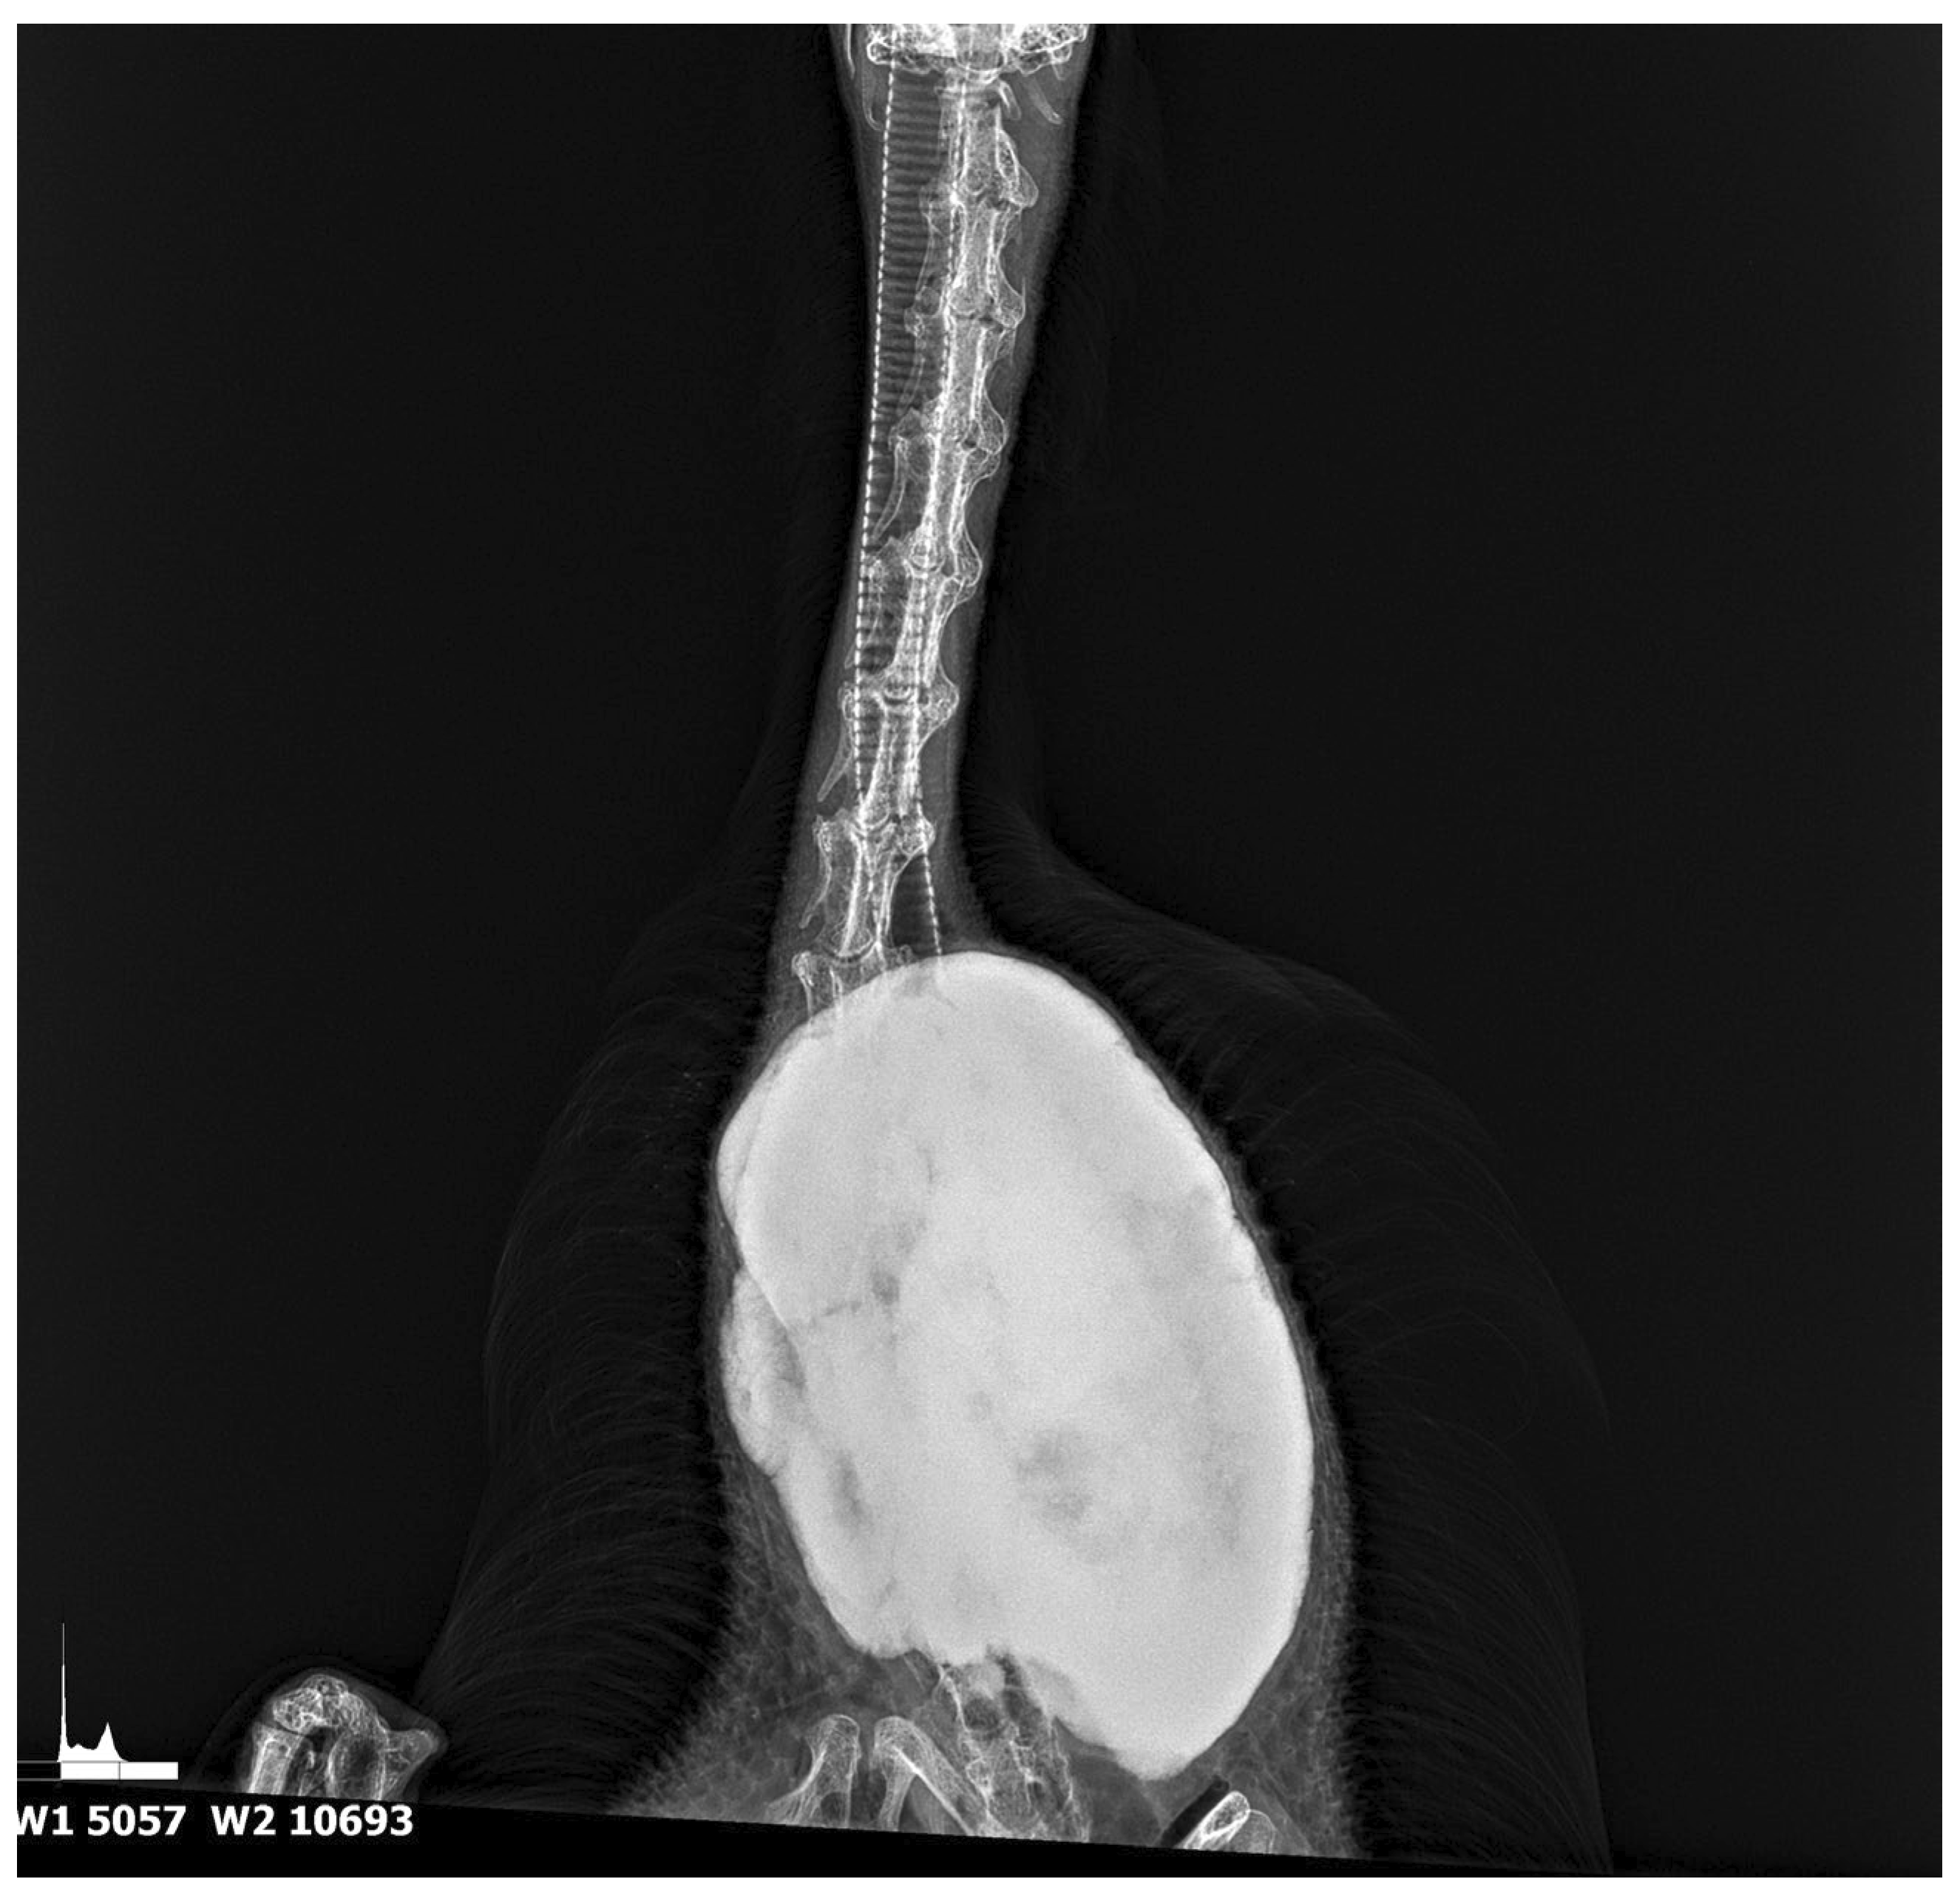

3.1. Results of Radiological Examination